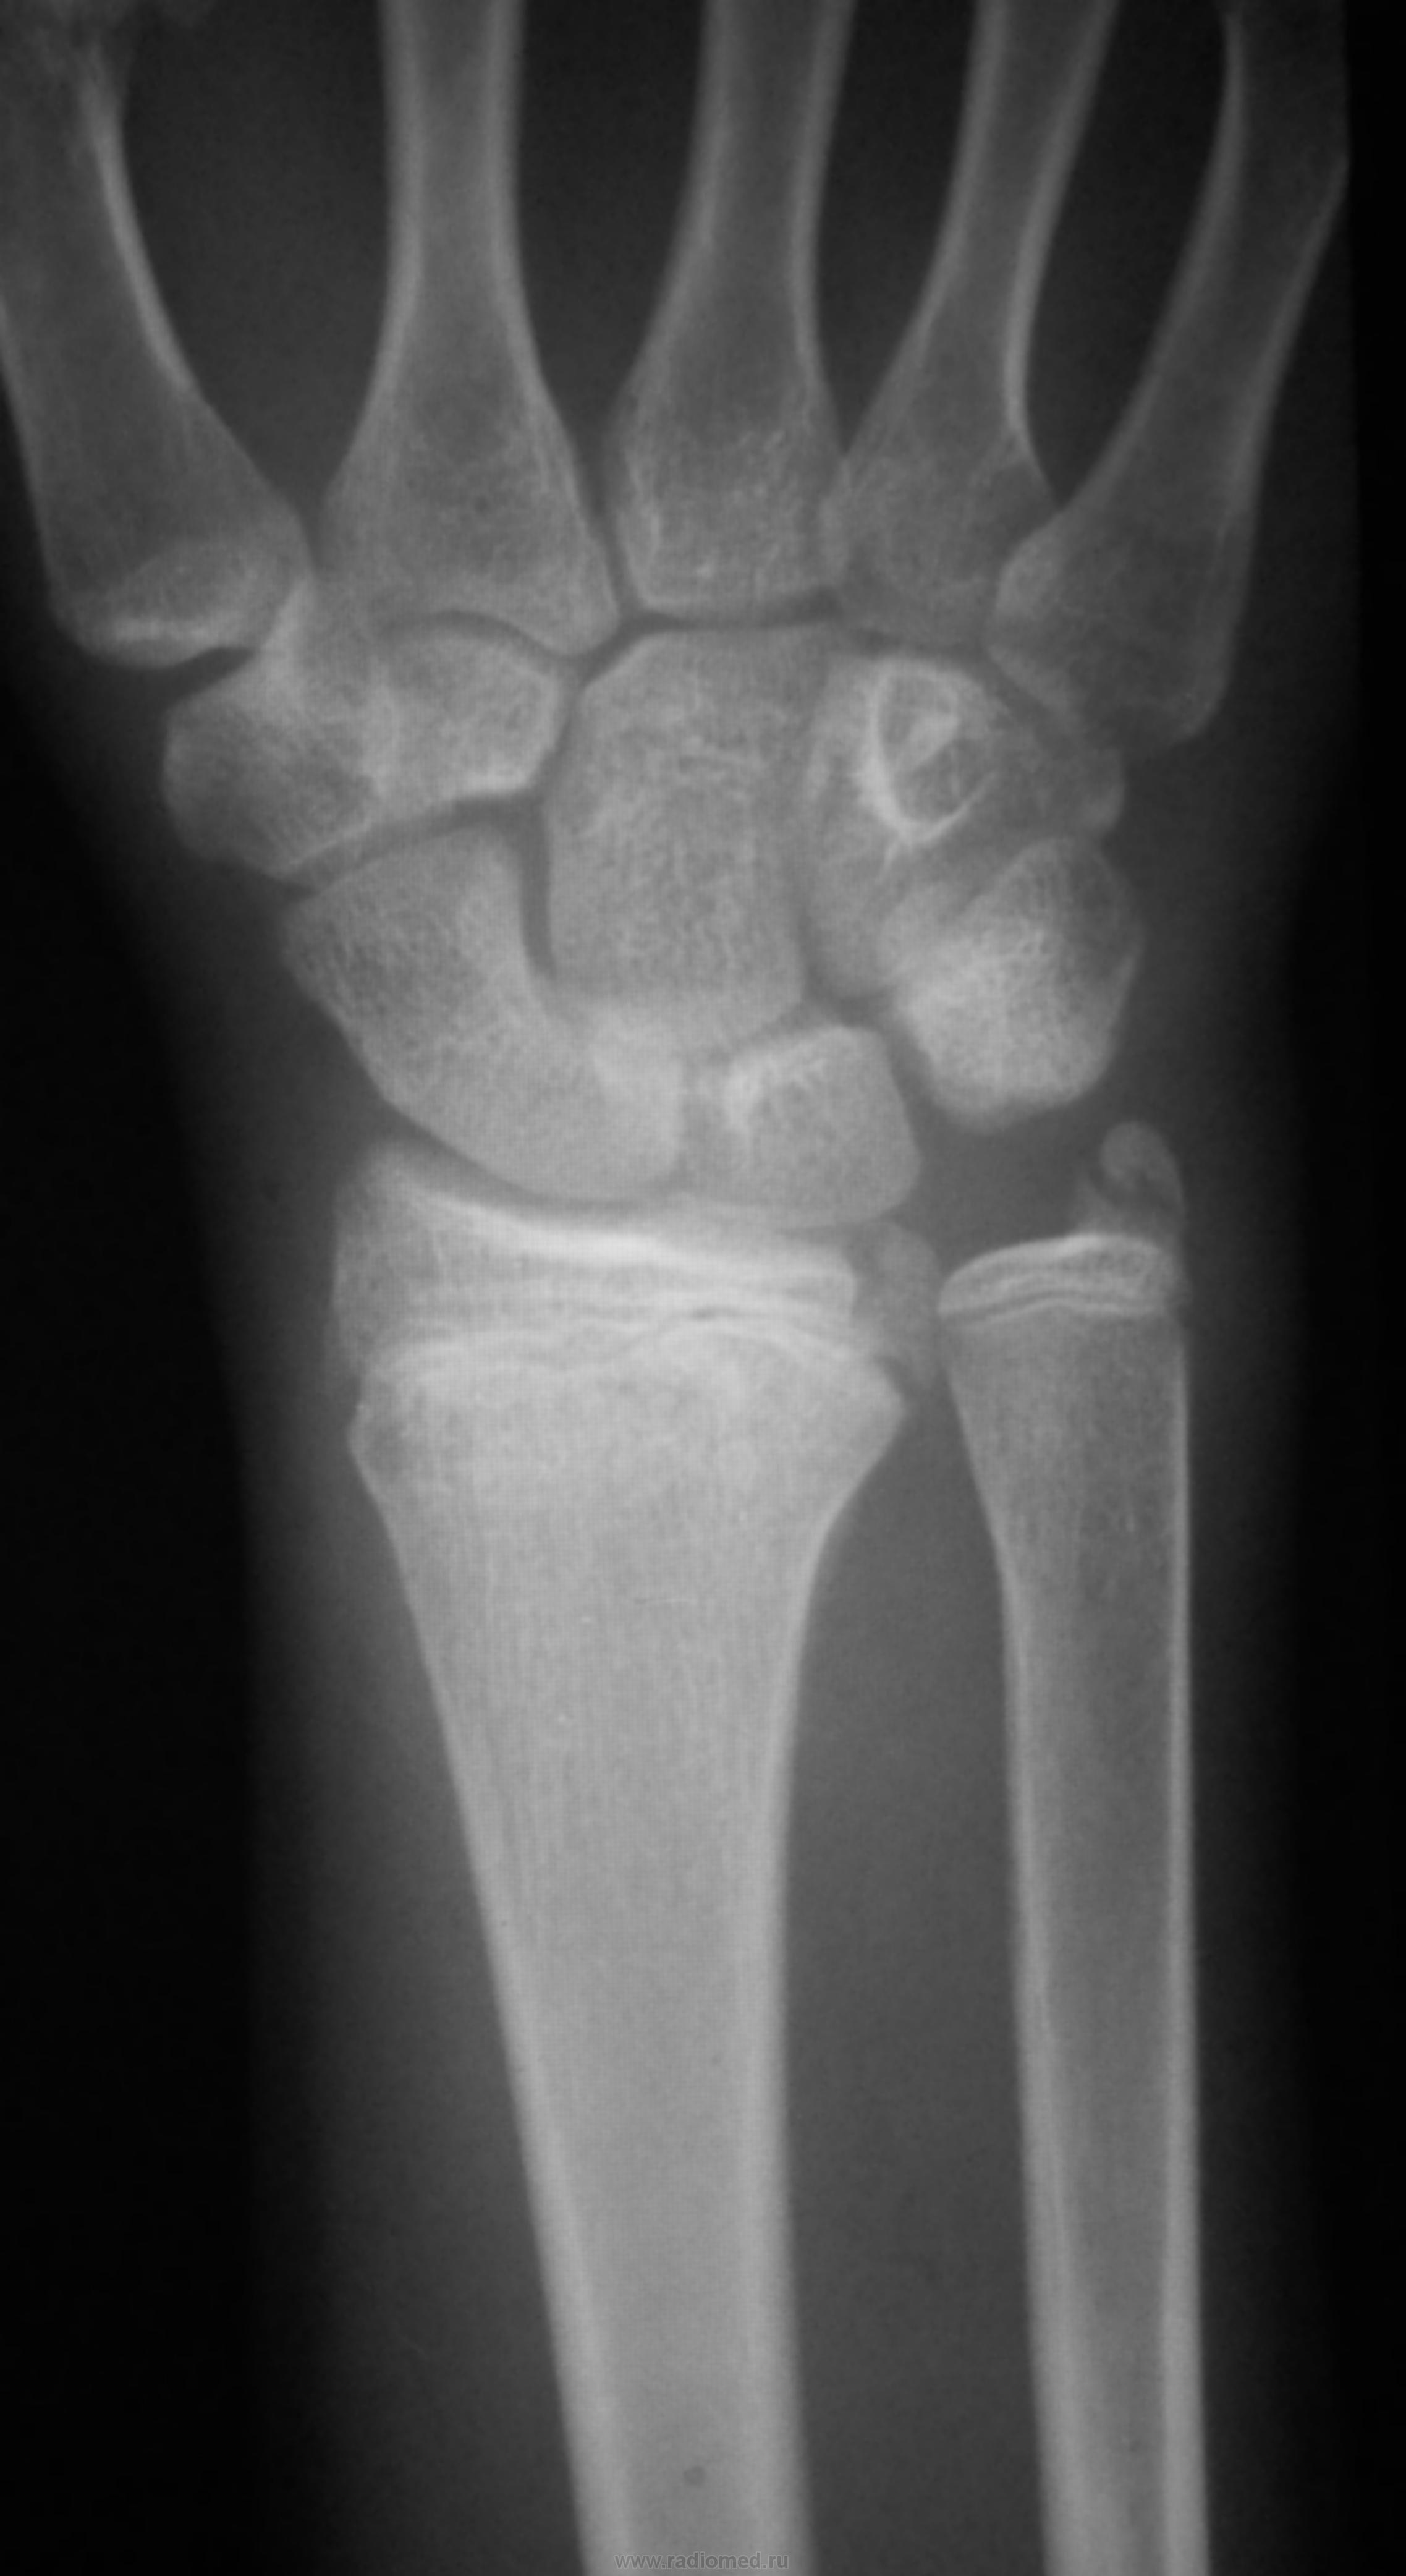

Оскольчатый перелом эпифиза лучевой кости с переходом на продольный перелом метафиза. Отрыв шиловидного отростка локтевой кости.

Поперечный перелом метафиза с тыльным угловым смещением. С эпифизами... не спорю.

Неоднозначно всё